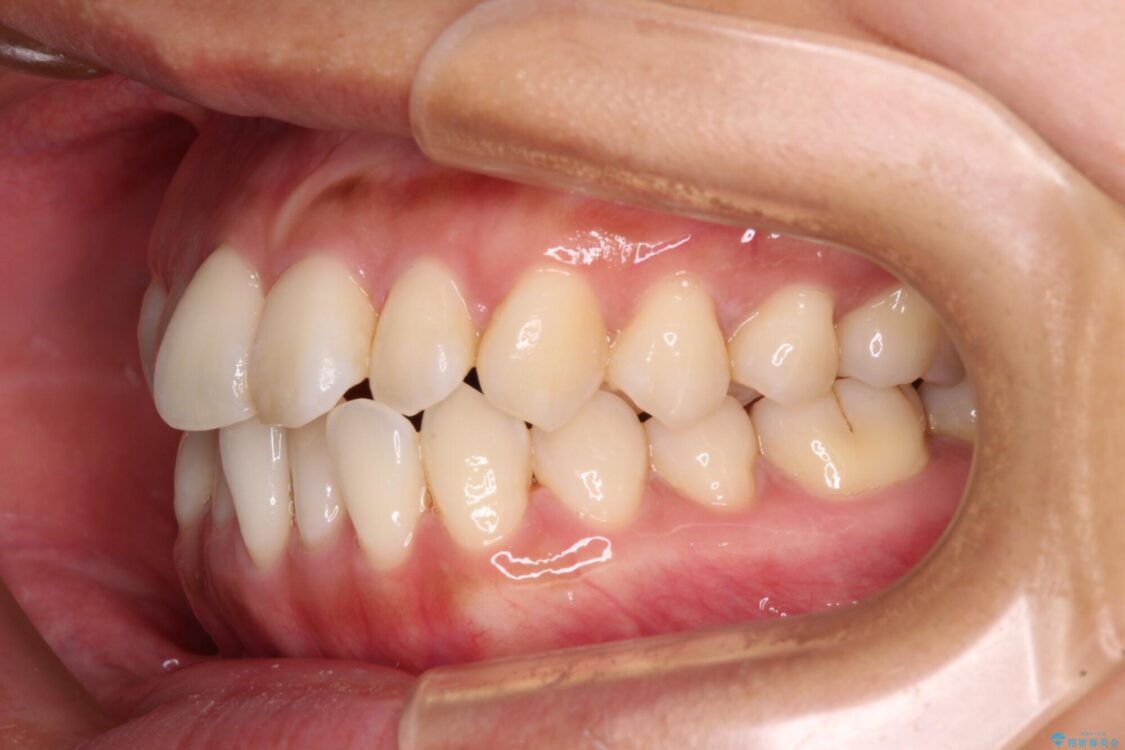

前歯のデコボコで前方に出ていることを気にして来院された患者様です。

上顎前歯が捻れて前方に飛び出しており、下顎前歯もそれに沿うようにデコボコとなっていました。

IPR(歯と歯の間を削る処置)によりスペースを獲得して上下顎前歯のデコボコを改善し、飛び出している前歯が引っ込むように設定し、インビザラインにて矯正治療を行うこととしました。

• 【モニター】前歯のデコボコをインビザラインで改善 治療前画像